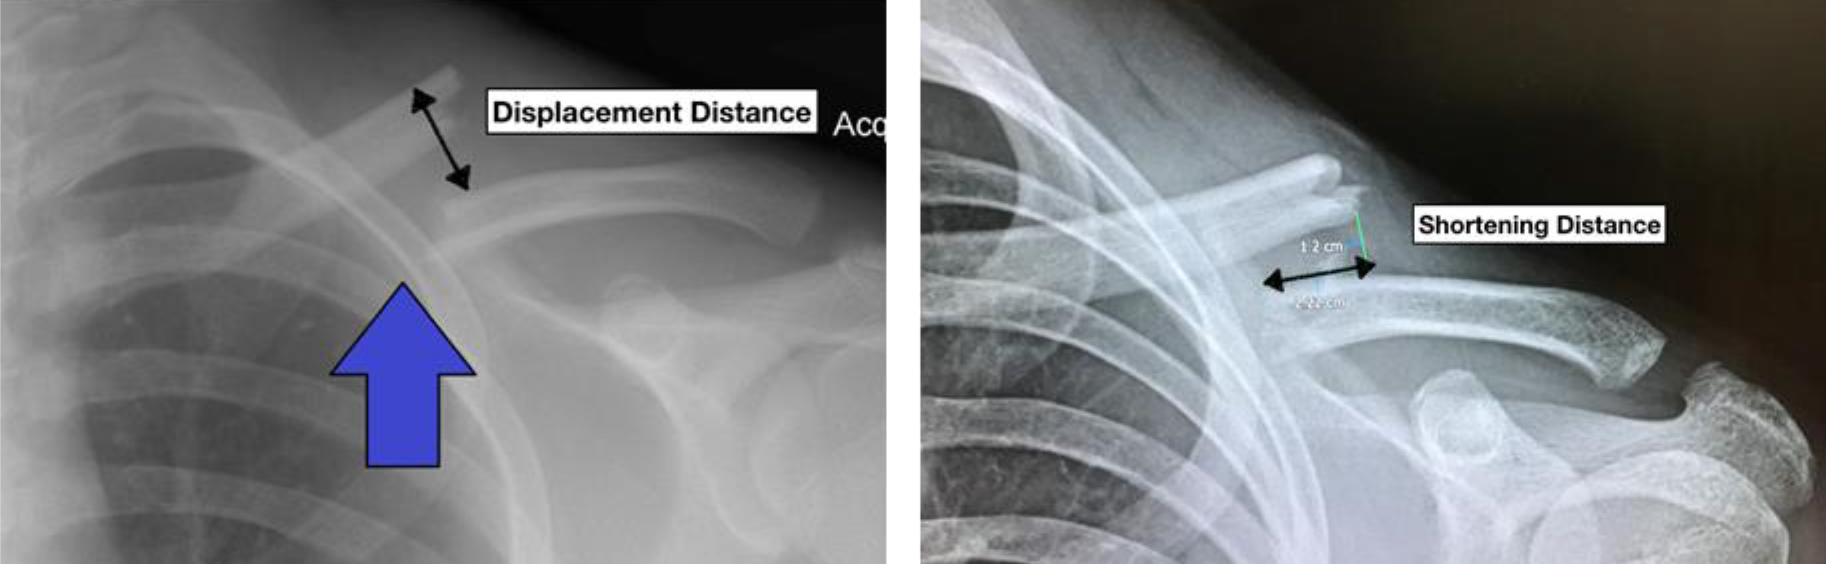

1. มีกระดูกห่างกันเกิน 2 ซม.

2. มีการหดสั้น(เหลื่อมซ้อนกัน)เกิน 2 ซม.